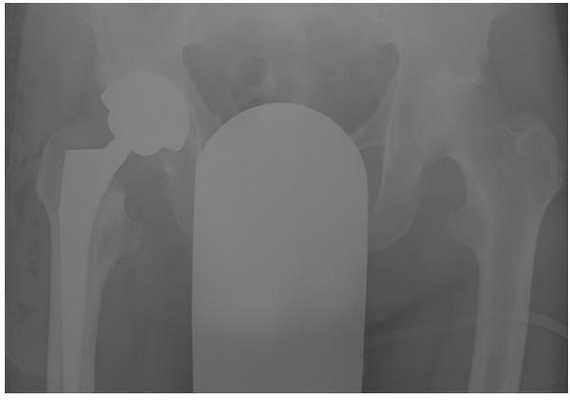

Выполнено тотальное эндопротезирование правого тазобедренного сустава эндопротезом фирмы Zimmer бесцементной фиксации, пара трения керамика\полиэтилен. Гладкое течение послеоперационного периода.

Рентгеногграммы после операции, положение компонентов эндопротеза правильное. Пациент активизирован на следующий день после операции, обучен ходьбе с дополнительной опорой на ходунки. Вторые сутки после операции, пациент ходит по палате и коридору без посторонней помощи с дополнительной опорой на ходунки.

Пациент выписан на 4 сутки после операции в удовлетворительном состоянии. В настоящее время функция опоры и ходьбы полностью восстановлена, ходит без дополнительной опоры, боли не беспокоят, восстановился нормальный стереотип походки.